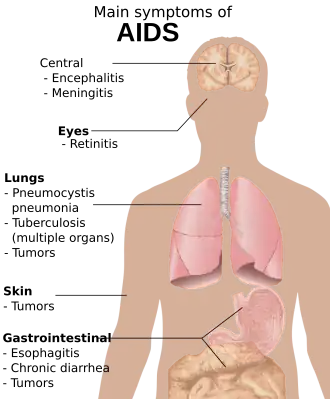

The stages of HIV infection are acute infection (also known as primary infection), latency, and AIDS. Acute infection lasts for several weeks and may include symptoms such as fever, swollen lymph nodes, inflammation of the throat, rash, muscle pain, malaise, and mouth and esophageal sores. The latency stage involves few or no symptoms and can last anywhere from two weeks to twenty years or more, depending on the individual. AIDS, the final stage of HIV infection, is defined by low CD4+ T cell counts (fewer than 200 per μL), various opportunistic infections, cancers, and other conditions.

The symptoms of AIDS are primarily the result of conditions that do not normally develop in individuals with healthy immune systems. Most of these conditions are opportunistic infections caused by bacteria, viruses, fungi, and parasites that are normally controlled by the elements of the immune system that HIV damages.[11] These infections affect nearly every organ system.

People with AIDS also have an increased risk of developing various cancers such as Kaposi's sarcoma, cervical cancer, and cancers of the immune system known as lymphomas. Additionally, people with AIDS often have systemic symptoms of infection like fevers, sweats (particularly at night), swollen glands, chills, weakness, and weight loss.[13][14] The specific opportunistic infections that AIDS patients develop depend in part on the prevalence of these infections in the geographic area in which the patient lives.

Pulmonary

Pneumocystis pneumonia (PCP) (originally known as Pneumocystis carinii pneumonia) is relatively rare in healthy, immunocompetent people, but common among HIV-infected individuals.[15] It is caused by Pneumocystis jirovecii.

Tuberculosis (TB) is unique among infections associated with HIV because it is transmissible to immunocompetent people via the respiratory route, and it is not easily treatable once identified.[17] Multidrug resistance is a serious problem. Tuberculosis with HIV co-infection (TB/HIV) is a major world health problem according to the World Health Organization: in 2007, 456,000 deaths among incident TB cases were HIV-positive, a third of all TB deaths and nearly a quarter of the estimated 2 million HIV deaths in that year.[18] Even though its incidence has declined because of the use of directly observed therapy and other improved practices in Western countries, this is not the case in developing countries where HIV is most prevalent. In early-stage HIV infection (CD4 count >300 cells per μL), TB typically presents as a pulmonary disease. In advanced HIV infection, TB often presents atypically with extrapulmonary (systemic) disease a common feature. Symptoms are usually constitutional and are not localized to one particular site, often affecting bone marrow, bone, urinary and gastrointestinal tracts, liver, regional lymph nodes, and the central nervous system.[19]

Esophagitis is an inflammation of the lining of the lower end of the esophagus (gullet or swallowing tube leading to the stomach). In HIV-infected individuals, this is normally due to fungal (candidiasis) or viral (herpes simplex-1 or cytomegalovirus) infections. In rare cases, it could be due to mycobacteria.[20]

Unexplained chronic diarrhea in HIV infection is due to many possible causes, including common bacterial (Salmonella, Shigella, Listeria or Campylobacter) and parasitic infections; and uncommon opportunistic infections such as cryptosporidiosis, microsporidiosis, Mycobacterium avium complex (MAC) and viruses,[21] astrovirus, adenovirus, rotavirus and cytomegalovirus, (the latter as a course of colitis).

Toxoplasmosis is a disease caused by the single-celled parasite Toxoplasma gondii; it usually infects the brain, causing toxoplasma encephalitis, but it can also infect and cause disease in the eyes and lungs.[24] Cryptococcal meningitis is an infection of the meninx (the membrane covering the brain and spinal cord) by the fungus Cryptococcus neoformans. It can cause fevers, headache, fatigue, nausea, and vomiting. Patients may also develop seizures and confusion; left untreated, it can be lethal.

People with HIV infections have substantially increased incidence of several cancers. This is primarily due to co-infection with an oncogenic DNA virus, especially Epstein-Barr virus (EBV), Kaposi's sarcoma-associated herpesvirus (KSHV) (also known as human herpesvirus-8 [HHV-8]), and human papillomavirus (HPV).[30][31]

Kaposi's sarcoma (KS) is the most common tumor in HIV-infected patients. The appearance of this tumor in young homosexual men in 1981 was one of the first signals of the AIDS epidemic. Caused by a gammaherpes virus called Kaposi's sarcoma-associated herpes virus (KSHV), it often appears as purplish nodules on the skin, but can affect other organs, especially the mouth, gastrointestinal tract, and lungs. High-grade B cell lymphomas such as Burkitt's lymphoma, Burkitt's-like lymphoma, diffuse large B-cell lymphoma (DLBCL), and primary central nervous system lymphoma present more often in HIV-infected patients. These particular cancers often foreshadow a poor prognosis. Epstein-Barr virus (EBV) or KSHV cause many of these lymphomas. In HIV-infected patients, lymphoma often arises in extranodal sites such as the gastrointestinal tract.[32] When they occur in an HIV-infected patient, KS and aggressive B cell lymphomas confer a diagnosis of AIDS.